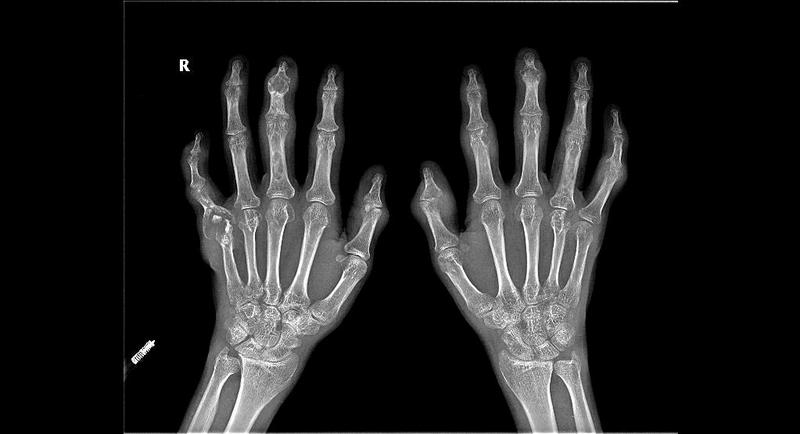

28岁的胡先生全身多处关节疼痛长达13年,尤其双膝肿胀严重,曾一度丧失劳动力。近日,南方医科大学中西医结合医院风湿病科肖长虹主任团队予其中西医结合治疗,在规范西药治疗的基础上,同时给予中药外敷、熏蒸治疗等,并对患者双膝关节行微创针刀镜手术和左外踝巨大痛风石切除术。